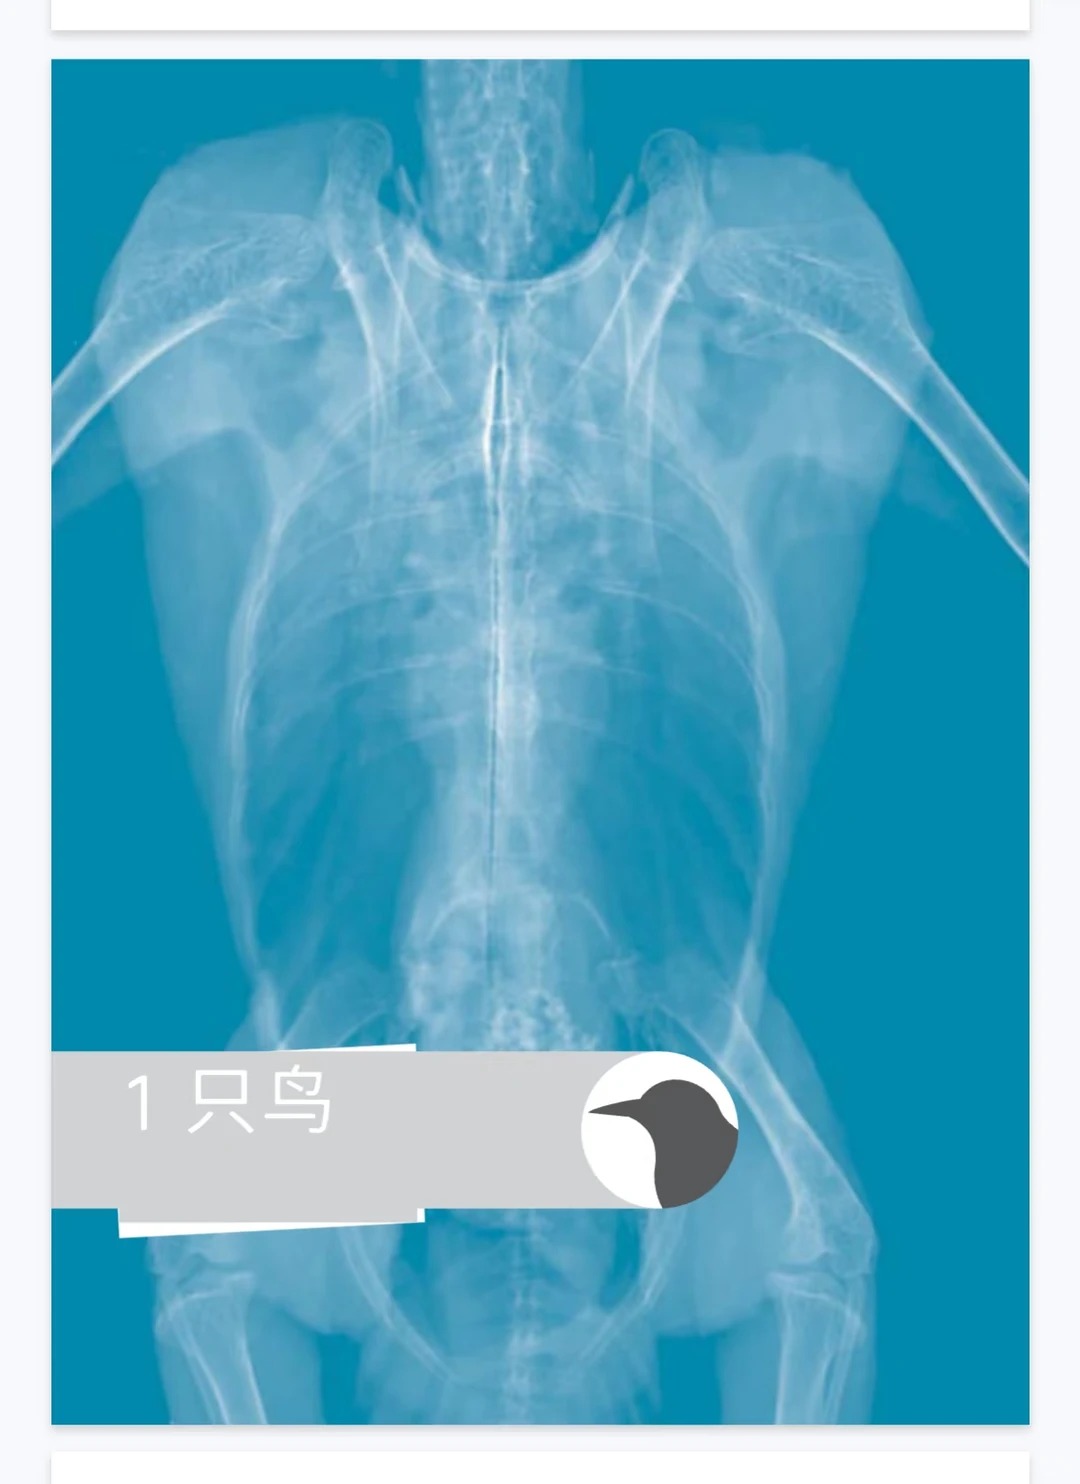

3. 插图高清,标注清晰 全书收录1400+张高清影像插图,超清画质,每张图都有清晰的解剖结构标注,直观呈现正常与病变的差异,快速区分病症,提升诊断准确性,适合新手快速上手。

• 核心内容:《最新中文版异宠影像诊断学》(《Diagnostic Imaging of Exotic Pets: Birds, Small Mammals, Reptiles》)PDF电子版,异宠兽医领域宝藏工具书;覆盖鸟类、爬宠(蜥蜴、蛇、龟)、小型哺乳动物(兔子、啮齿类),系统解读X光、超声、CT、MRI等主流影像技术,收录1400+张高清影像插图(标注清晰),按物种+器官系统分章节,每章附设备要求、安全注意事项等临床干货,提供中文版(AI+人工)+中英对照版,超清画质。